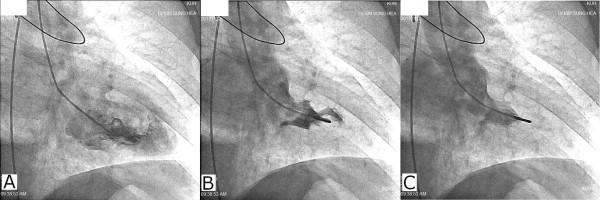

A 65-year-old man with hypertension presented himself at the emergency department with syncope after chest pain. His initial electrocardiography showed inferior ST elevation with profound precordial ST depression and transient complete atrioventricular block. Due to sustained hypotension, an intra-aortic balloon pump was applied. His coronary angiography revealed almost normal right coronary artery and left circumflex artery and only a severe myocardial bridge in the mid-segment of his left anterior descending artery. Instead, severe mitral regurgitation was found without regional wall motion abnormality both in the left ventriculography and the portable echocardiography. However the severe mitral regurgitation completely disappeared in follow up echocardiography the day after. The pressure gradient across the left ventricular outflow tract was measured at 8.95 mmHg during the resting state, and was increased to 38.95 mmHg during the Valsalva state.

一名65岁高血压男性因胸痛后晕厥就诊于急诊科。其初始心电图显示下壁ST段抬高伴胸前导联ST段显著压低及短暂完全性房室传导阻滞。因持续性低血压,应用了主动脉内球囊反搏。其冠状动脉造影显示右冠状动脉和左旋支动脉几乎正常,仅左前降支动脉中段有严重心肌桥。相反,左心室造影和便携式超声心动图均显示严重二尖瓣反流但无节段性室壁运动异常。然而,次日的随访超声心动图显示严重二尖瓣反流完全消失。静息状态下左心室流出道压差为8.95 mmHg,瓦尔萨尔瓦动作时增至38.95 mmHg。